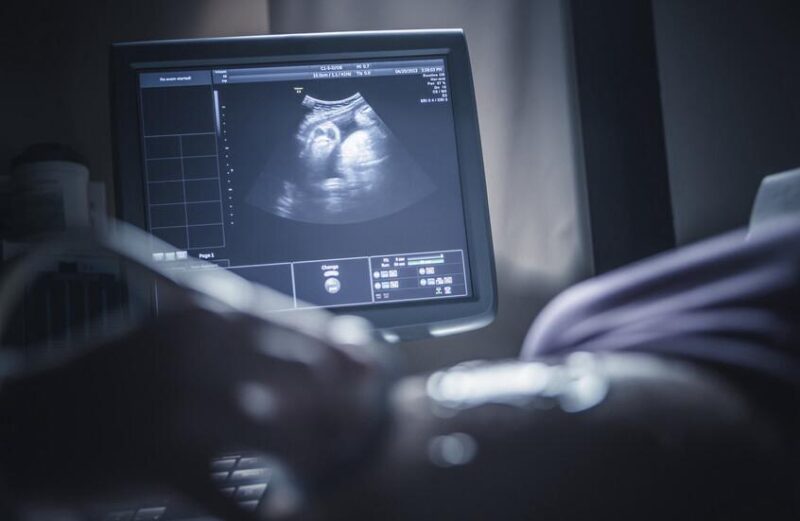

واعتمدت الدراسة على فحوصات بالرنين المغناطيسي لـ132 طفلاً خلال شهرهم الأول، وأظهرت ارتباطاً واضحاً بين ارتفاع الجسيمات الدقيقة وتراجع الميالينة.